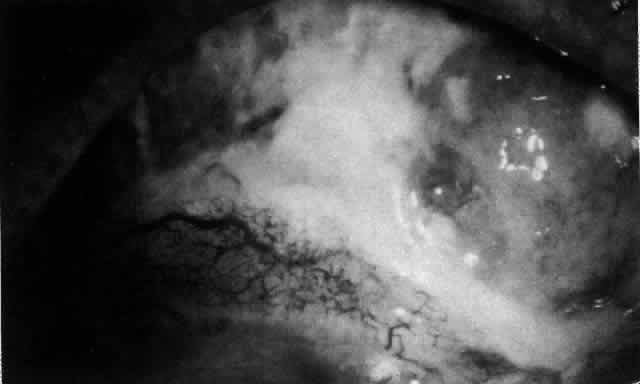

The characteristic features of necrotizing scleritis on fluorescein angiography are hypoperfusion and, eventually, nonperfusion of the vascular networks (Figs. 40 through 43).26 The initial changes are on the venous side of the capillary network; the transit time of the dye increases even if the eye is red and congested. If the disease process persists or has been present for a long time, thrombosis and permanent vaso-occlusive changes occur. These vessels (or the occluded capillary network) are bypassed by the opening of anastomotic channels. New vessels in a granuloma give rise to deep intrascleral leakage of dye (see Fig. 43). Conjunctival and episcleral involvement by the destructive change is late but is always preceded by vaso-occlusive changes that can sometimes be detected with use of the red-free light on the slit lamp (Figs. 44 and 45).

Fig. 41. Late stage of fluorescein angiogram adjacent to the site of necrosis in the same patient as in Figure 40. Although the eye is uniformly congested, the area near the necrosis shows vascular shutdown, whereas the rest of the conjunctiva and episclera is normally perfused.